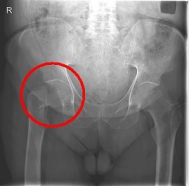

The femoral neck fracture is one of the most common fractures of the elderly. The cause is usually a fall on the hip from a low height. An important risk factor is osteoporosis.

In addition to a thorough physical examination, radiographs of the pelvis and the affected hip are crucial for the diagnosis.